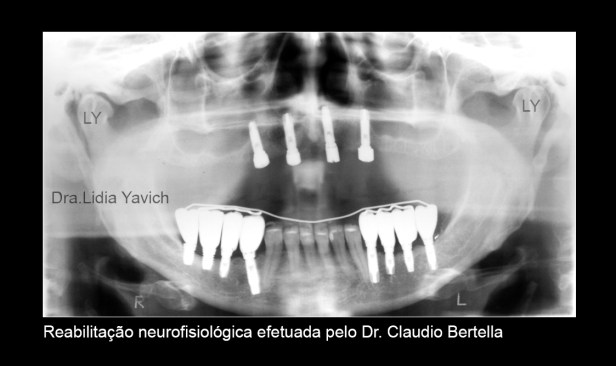

Terminado o tratamento de patologia da ATM encaminhei a paciente para o colega que fez a reabilitação neurofisiológica, mantendo a posição tridimensional obtida.

Os implantes tem mais de 5 anos de instalados.